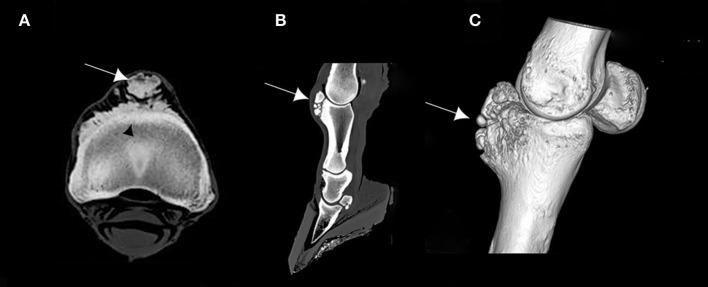

This study aimed at describing anatomo-histopathological and imaging features, using computed tomography and magnetic resonance imaging on six forelimbs of Tbourida horses, that presented a particular bone exostosis on the dorsal and proximal part of the first phalanx, diagnosed by X-ray. Gross anatomy of the bone exostosis revealed an irregular surface with poly-lobulated tissue masses showing a cauliflower shape. The diameter/depth varied from 0.5 to 5.1 cm with a mean of 3.9 ± 0.9 cm. The capsule of the metacarpophalangeal joint was hypertrophic and showed many invaginations in the inner part, in contact with the bone exostosis. Computed tomography revealed cortical and medullary continuity of the bone exostosis, with the underlying bone, and remodeling of the cortical surface of the dorsal and proximal part of the first phalanx. Magnetic resonance imaging showed an increased signal intensity of the bone exostosis on the T1- and T2-weighted gradient fast echo. Histological examination of the bone exostosis revealed a cap of hyaline cartilage, including large foci of endochondral ossification with a base of cancellous bone surrounding marrow spaces, which confirmed the diagnosis of osteochondroma. The capsule of the metacarpophalangeal joint showed a large amount of recently formed connective tissue fibers in its inner part, interspersed with mature connective tissue. The hyperextension of the metacarpophalangeal joint during a Tbourida show, which occurs on a hard ground surface, and the use of hobbles in horse stabling are most likely responsible for the outgrowth of an osteochondroma of different shapes and sizes, and fracture complications in some cases.

本研究旨在描述6匹图里达马前肢的解剖组织病理学和影像学特征,这些马的第一指骨背侧和近端出现了一种特殊的骨外生骨疣,通过X线诊断。骨外生骨疣的大体解剖显示其表面不规则,有多个分叶状组织块,呈菜花状。直径/深度在0.5至5.1厘米之间,平均为3.9±0.9厘米。掌指关节的关节囊肥厚,内部有许多内陷,与骨外生骨疣接触。计算机断层扫描显示骨外生骨疣与下方骨骼的皮质和髓质连续,第一指骨背侧和近端的皮质表面有重塑。磁共振成像显示在T1加权和T2加权梯度快速回波上骨外生骨疣的信号强度增加。骨外生骨疣的组织学检查显示有一层透明软骨帽,包括大量软骨内成骨灶,其底部为围绕骨髓腔的松质骨,这证实了骨软骨瘤的诊断。掌指关节的关节囊内部有大量新形成的结缔组织纤维,夹杂着成熟的结缔组织。图里达马表演期间在坚硬地面上发生的掌指关节过度伸展以及马厩中使用缰绳极有可能导致不同形状和大小的骨软骨瘤长出,在某些情况下还会引发骨折并发症。